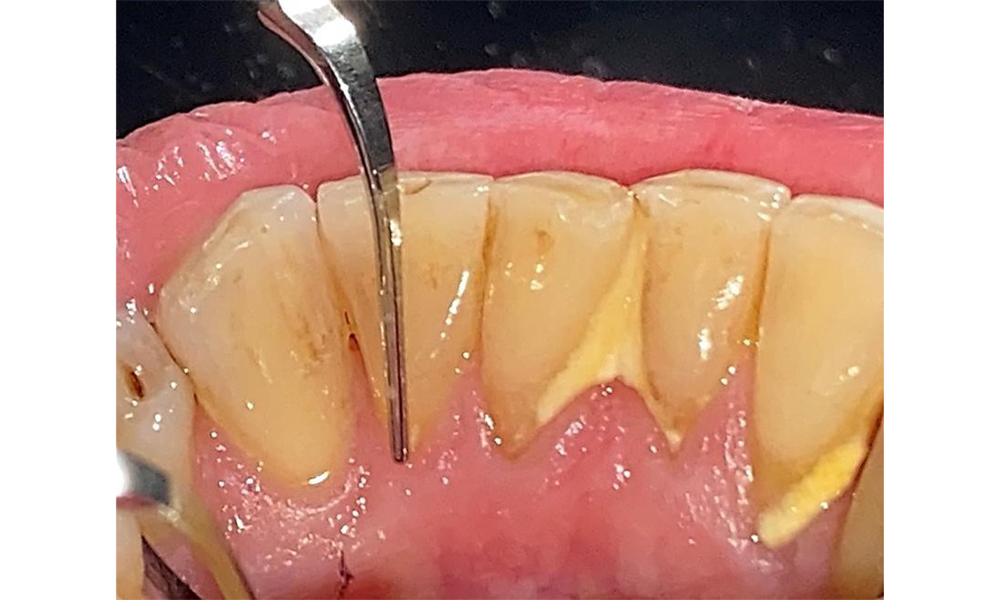

Der Patient hat eine Parodontitis Stadium II, Grad B (5). Die klinischen Sondierungstiefen liegen mit 1-3mm im physiologischen Bereich. Lokalisierte Sondierungstiefen finden sich an 17 und 27 jeweils mesiopalatinal mit 5mm. Es liegen generalisierte Rezessionen von 1-3mm vor mit partiellem Verlust der Interdentalpapillen (Abb. 2, Abb. 3, Abb. 4)

Der Patient ist ein gut eingestellter Diabetiker. Somit ergibt sich aus der Anamnese kein erhöhtes Komplikationsrisiko für die Behandlung. Grundsätzlich ist vor jeder Behandlung der HbA1c-Wert abzufragen. Die Befundaufnahme intraoral ist entscheidend für den Bedarf an dentaler und parodontaler Therapie. Aufgrund der Parodontitis ist ein parodontaler Befund mit Taschentiefensondierung und Blutungsstatus in jeder Sitzung unerlässlich (Abb. 8). Dieser gibt den individuellen Therapiebedarf vor und es kann auf eine mögliche Progression der parodontalen Vorerkrankung reagiert werden.

In der Instrumentierung sind bezüglich der Methodenwahl keine Einschränkungen gegeben. Aufgrund der parodontalen Vorerkrankung und dem hohen Rezidivrisikos ist die Vorbeugung einer Erkrankungsprogression durch die regelmäßige supra- und subgingivale Instrumentierung unerlässlich. Die Wahl der Instrumente zur mechanischen Biofilmentfernung ist aus allgemeingesundheitlicher Sicht nicht eingeschränkt und erfolgt bedarfsgerecht. Harte und mineralisierte Beläge wie Zahnstein und Konkremente sind mittels Handinstrumenten oder Schall/ Ultraschallscalern zu entfernen (Abb. 9) (8, 9).